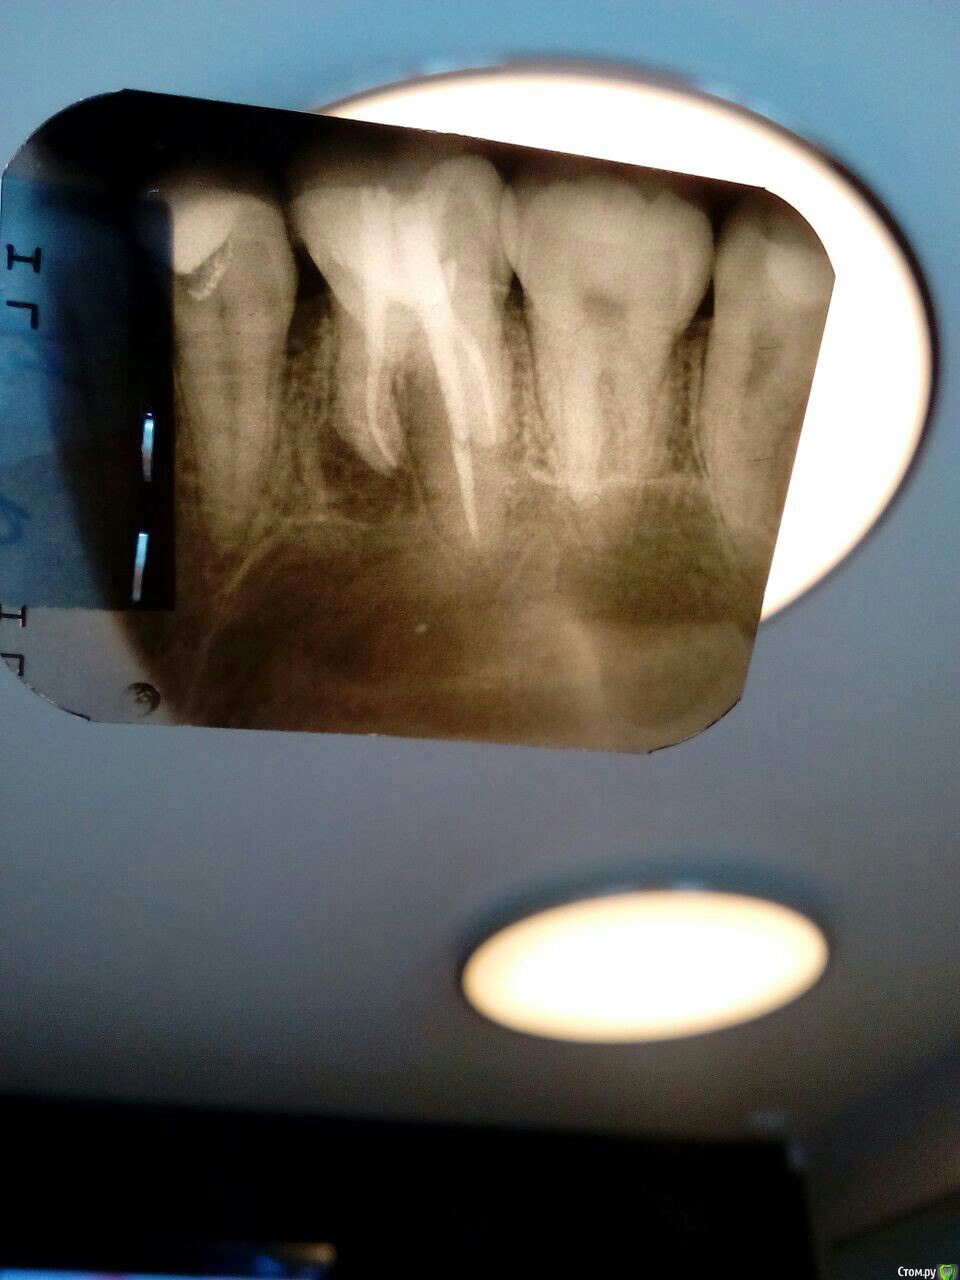

Подскажите стоит ли лечить 6 зуб или он на удаление? Знакомый говорит, что у него было так же. И что в медиально щёчном корне обычно 2 канала, и второй необработан, поэтому там киста.

как это понимать? судя по представленному снимку пятый зуб лечили по причине кариеса.

если судить только по снимку, то я за лечение с последующим протезированием.